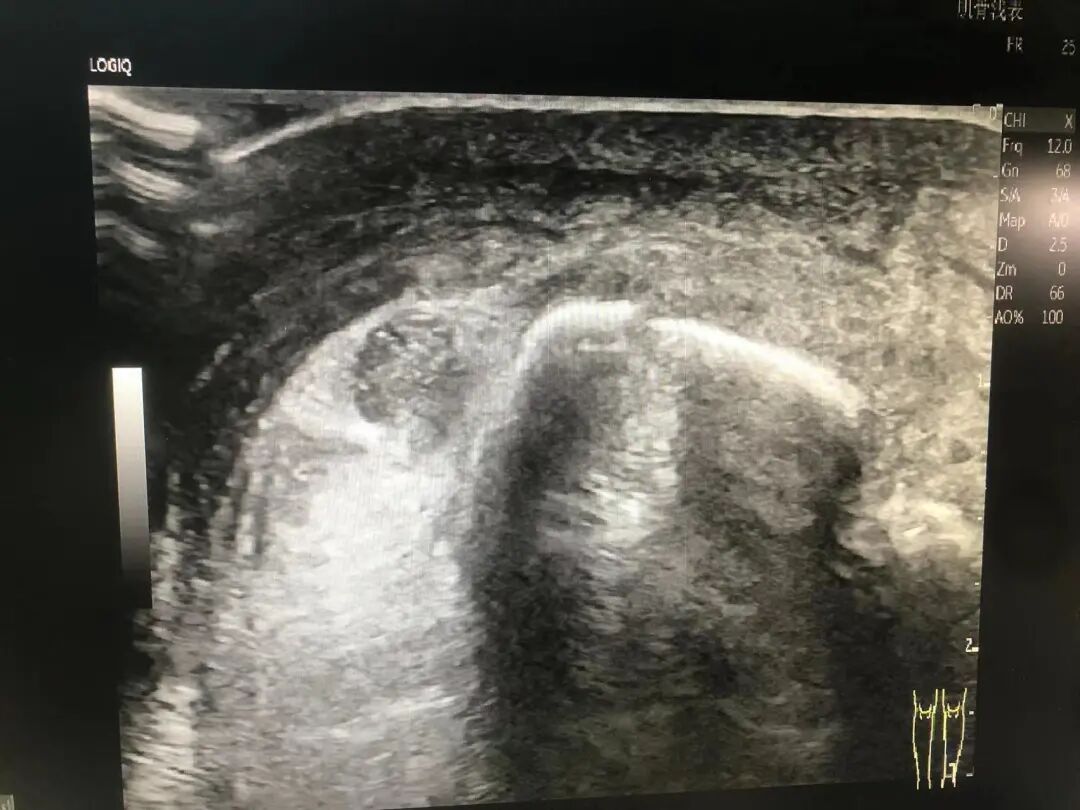

↑滑膜炎